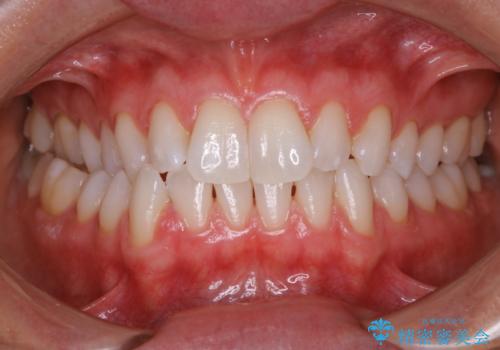

PMTCで笑った時の口元を自然に明るくしたい